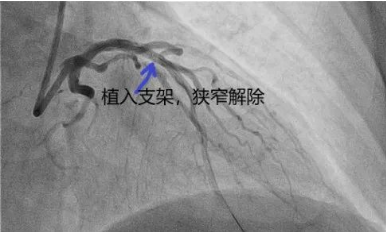

王大爷住院后,李钢主任和王志勇副主任医师第一时间为其完善冠脉造影检查,发现患者左前降支90%重度狭窄,给予球囊扩张后植入一枚支架,术后恢复良好,一周后康复出院,现能正常活动,无胸闷憋喘情况。